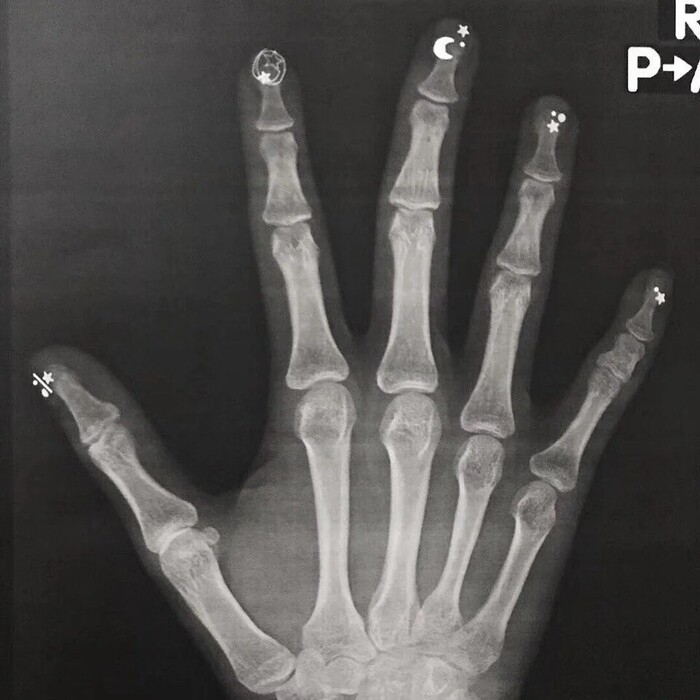

Немного интересных рентгеновских снимков ч.31